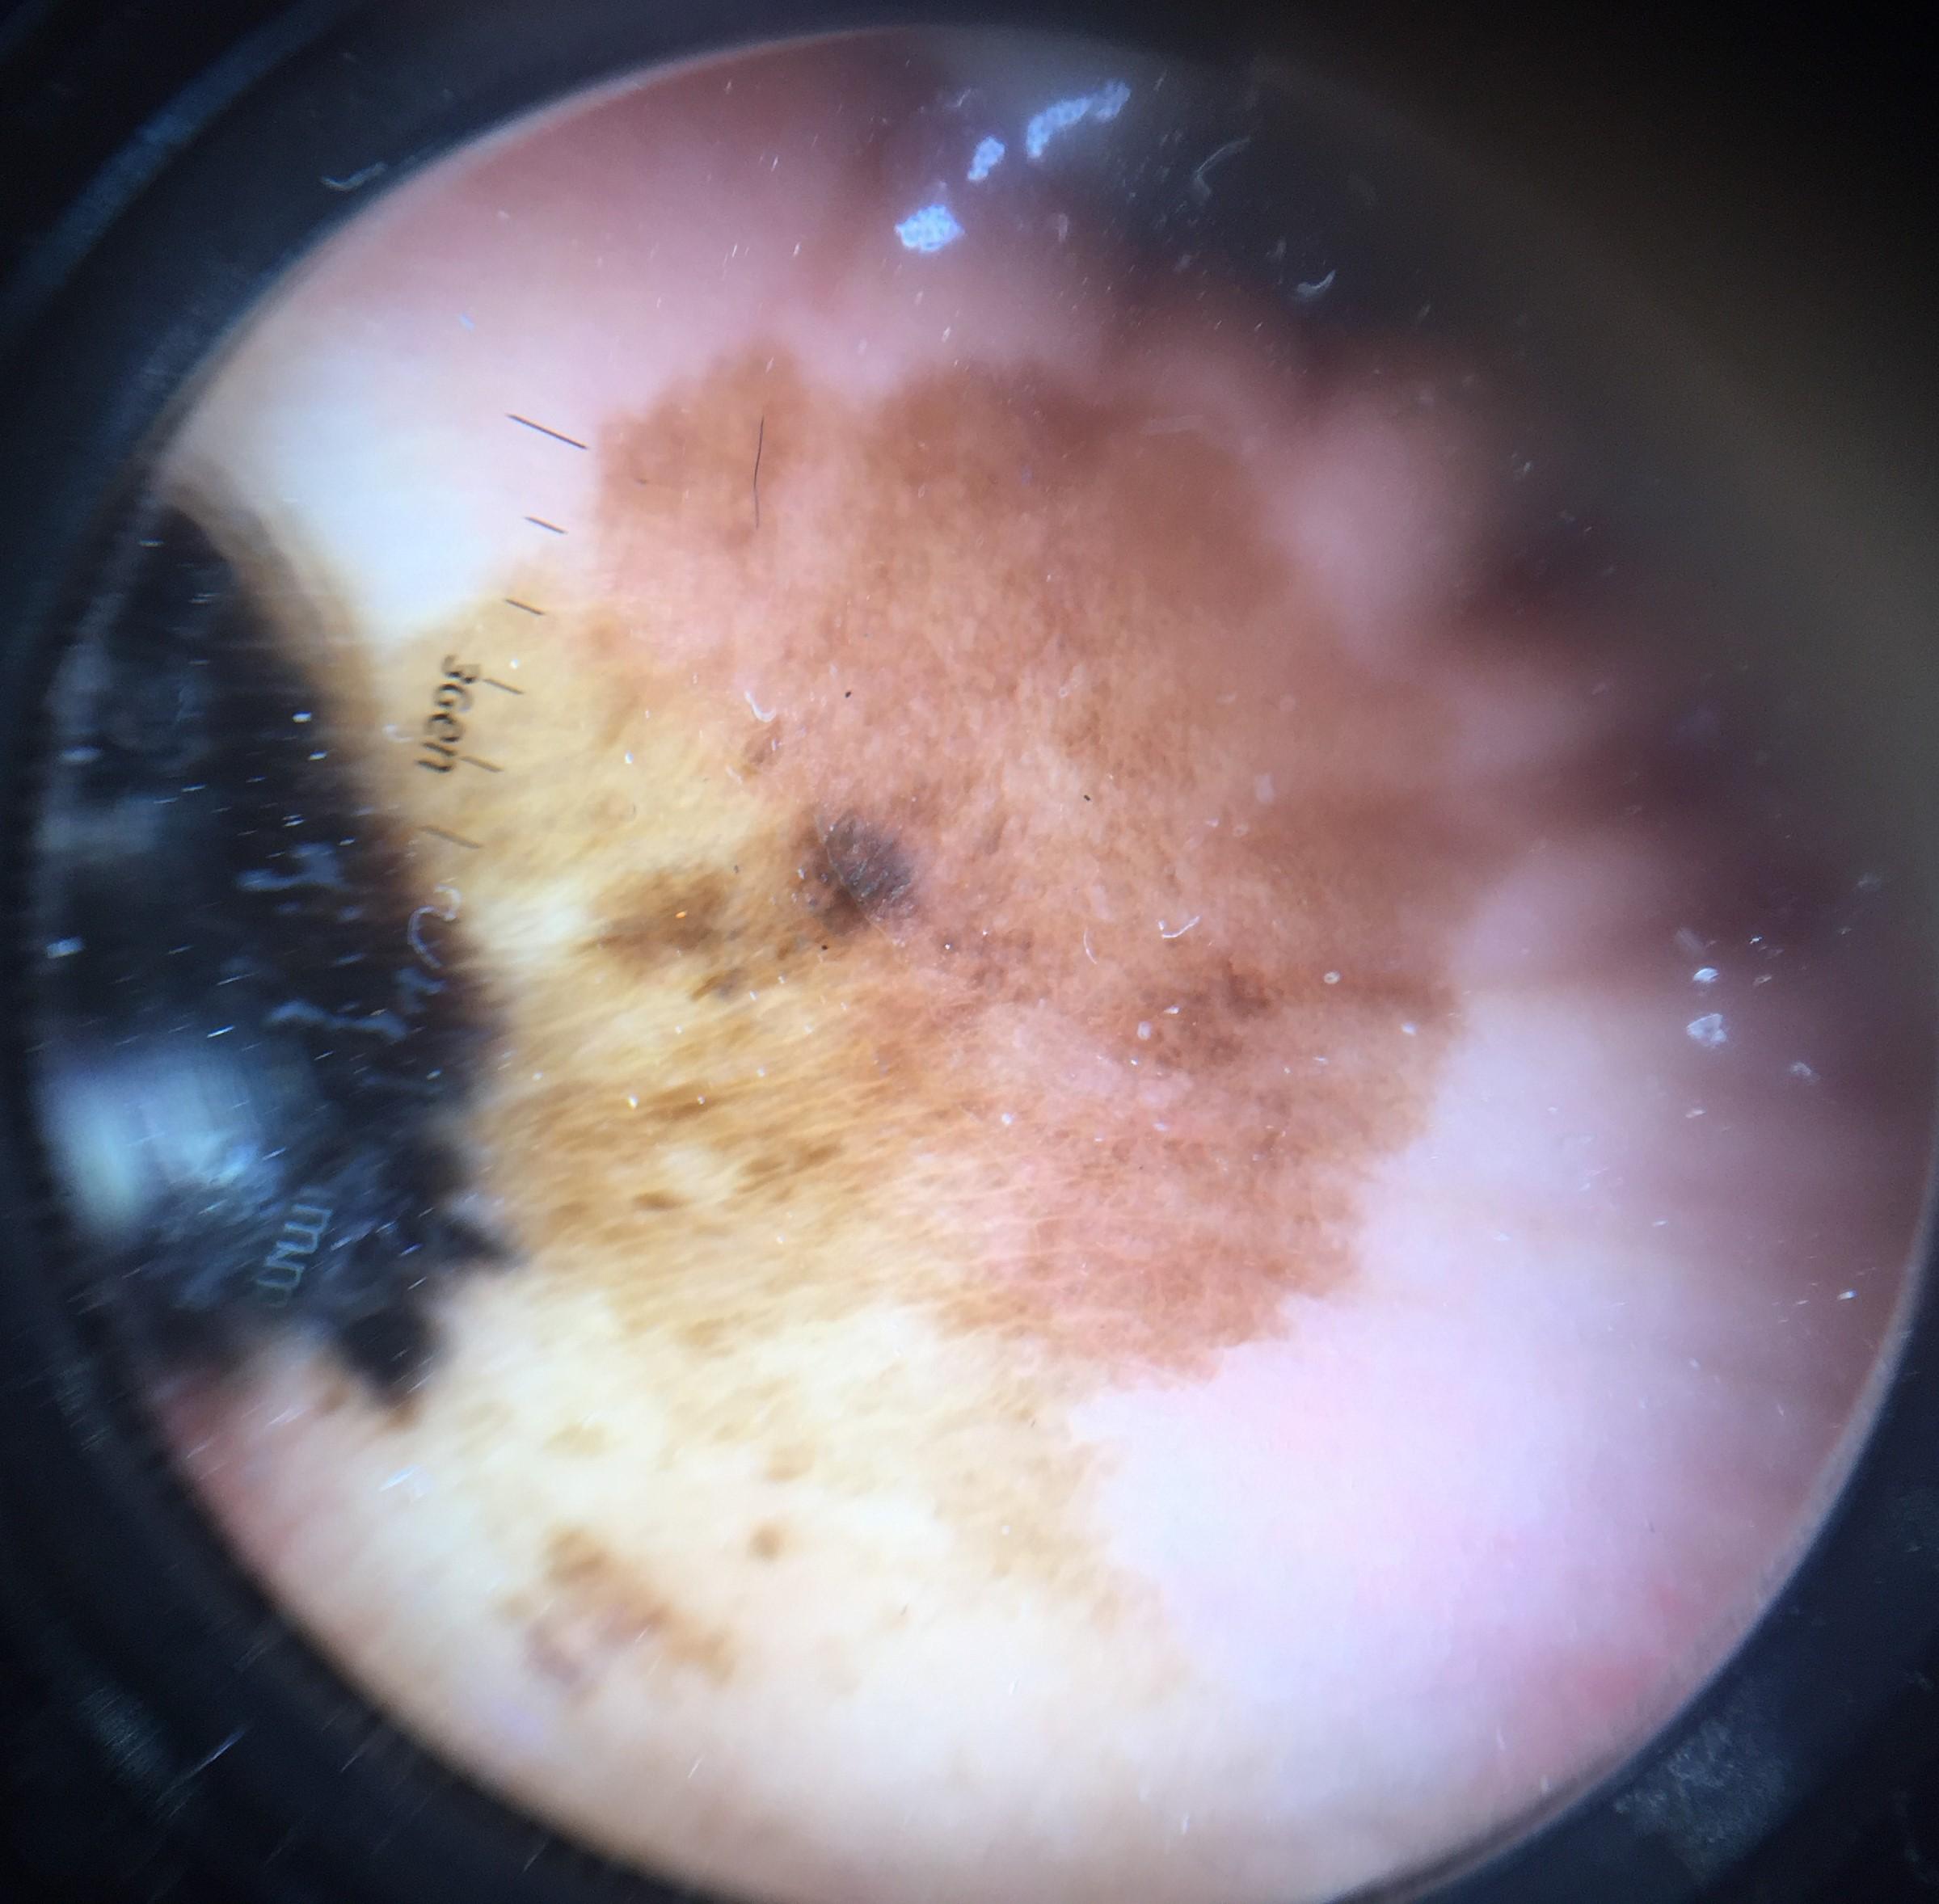

anatom_site_general palms/soles

anatom_site_special acral NOS

diagnosis_1 Malignant

diagnosis_2 Malignant melanocytic proliferations (Melanoma)

diagnosis_3 Melanoma, NOS

diagnosis_confirm_type histopathology

image_type dermoscopic

melanocytic True